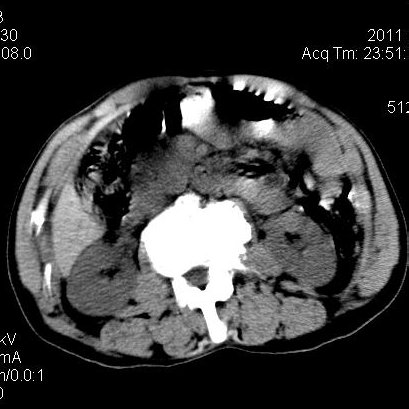

肝左叶发育异常

男性,55岁,骑摩托车摔倒后入院,自述右上腹疼痛

[backcolor=#FF0000]第一次诊断的时候也是这么肯定,可是床旁超声检查并没有发现明显异常,而且患者的一般症状都良好。还好临床只是保守治疗,没有立即手术,第二次复查的时候没有一点变化,又做了MRI检查,没有血肿,

这是一例肝左叶发育异常的,很个性吧~[/backcolor]